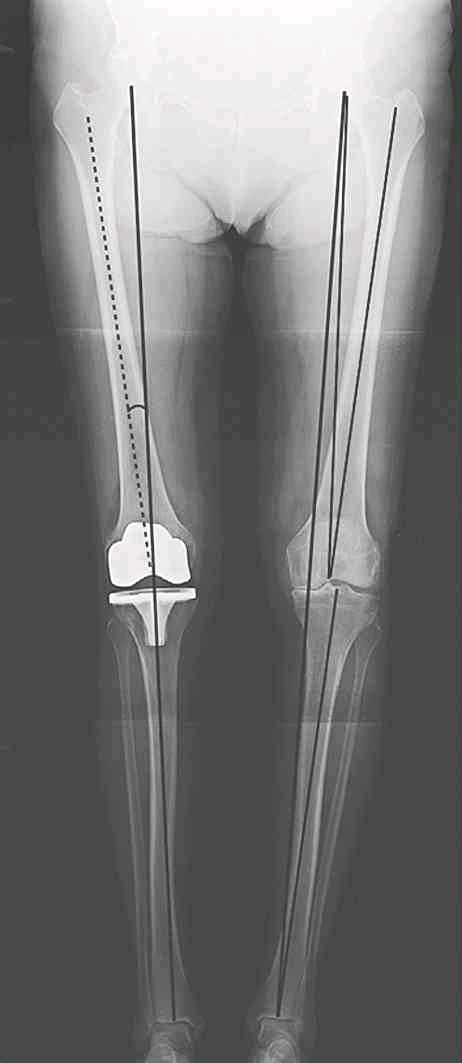

下肢轴线:

右下肢为关节置换术后,下肢力线与胫骨机械轴重叠;左下肢为未置换,下肢对线不良,膝关节内翻

(1)下肢机械轴(mechanical axis of the lower extremity):

也称下肢力线,即股骨头中心至踝关节中心的连线。假如该线经过膝关节中心点,则股骨机械轴将与胫骨机械轴相重叠。

(2)股骨机械轴(mechanical axis of the femur):

股骨头中心至膝关节中心的连线。

(4)胫骨机械轴(mechanical axis of the tibia):

膝关节中心至踝关节中心的连线。